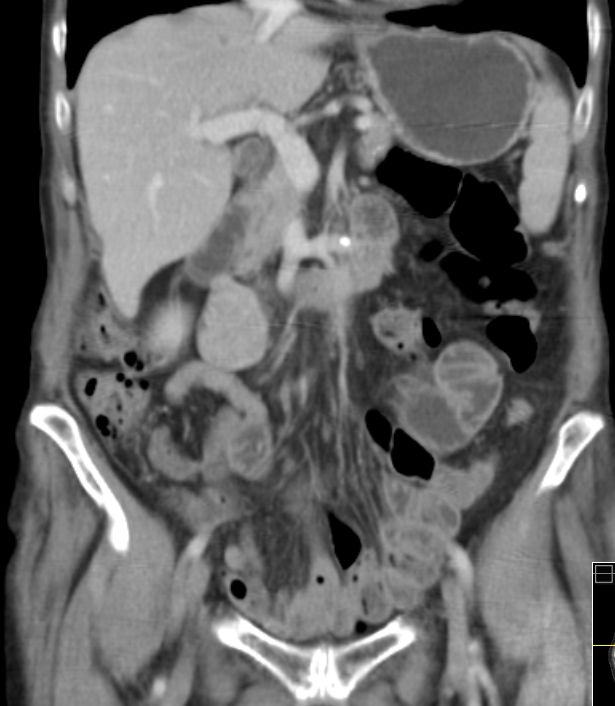

78-jähriger Mann, der 2 Jahre nach GIST des Dünndarms Lebermetastasen entwickelte.

Typisch ist die ausgeprägte hypervaskuläre Metastasenperipherie.![]() |

60-jähriger Mann, der vor 12 Jahren ein GIST mit Befall von Magen und Quercolon hatte.

Seit 8 Jahren Lebermetastasen.

Therapie mit Imatinib, jetzt Sunitinib:SD.![]() | |||||||||||||||||||||||||||||||||||||||